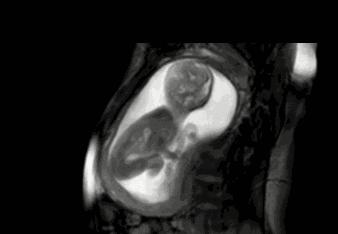

在孕妈的一整个孕期都有很多需要注意的地方,尤其是随着胎儿的逐渐长大,不可能每天都去医院检查胎宝是否健康,此时数胎动就成为孕妈观察胎宝健康状况的一个重要举动。只是,作为新手孕妈,你真的会数胎动吗?

胎儿在孕妈肚子里的动作都是不一定的,有可能用脚踢一下,有可能用手锤一下,小雨就是将这每一个动作都计算为一次胎动。其实真正的一次胎动,是胎宝的一个连续的动作。一般这个计算时长在一分钟左右,或者在隔了有五分钟以上,再有胎动的时候记为第二次胎动。

有些孕妈比较心急,从20周,甚至16周就开始数胎动,其实这个月份数下来并不是很准。因为在这个阶段,孩子的胎动并不是很明显,频率也比较低。一般建议是在28周,也就是胎儿七个月的时候,孕妈开始数胎动。这个时间段的胎动最为活跃,孕妈也最需要注意胎儿的健康。